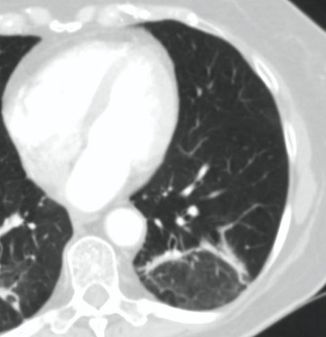

Методы лучевой диагностики применяют для выявления COVID-19 пневмоний, их осложнений, дифференциальной диагностики с другими заболеваниями легких, а также для определения степени выраженности и динамики изменений, оценки эффективности проводимой терапии.

КТ имеет высокую чувствительность в выявлении изменений в легких, характерных для COVID-19. Применение КТ целесообразно для первичной оценки состояния ОГК у пациентов с тяжелыми прогрессирующими формами заболевания, а также для дифференциальной диагностики выявленных изменений и оценки динамики процесса. КТ позволяет выявить характерные изменения в легких у пациентов с COVID-19 еще до появления положительных лабораторных тестов на инфекцию с помощью МАНК. В то же время, КТ выявляет изменения легких у значительного числа пациентов с бессимптомной и легкой формами заболевания, которым не требуется госпитализация. Результаты КТ в этих случаях не влияют на тактику лечения и прогноз заболевания при наличии лабораторного подтверждения COVID-19. Поэтому массовое применение КТ для скрининга асимптомных и легких форм болезни не рекомендуется.

15. Рекомендации по формированию описаний и оценке изменений в легких и ОГК при имеющейся/подозреваемой пневмонии COVID-19 представлены в Приложении 1.